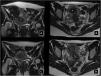

Procedimiento EAUEl conocimiento de la anatomía vascular de la pelvis femenina y sus anastomosis es fundamental para evitar complicaciones (fig. 2). El procedimiento se puede realizar bajo sedación consciente. El acceso arterial se consigue a través de la punción de la arteria femoral común o arteria radial, utilizando un introductor de 4-6 French (Fr) para el acceso femoral y de 4-5 Fr para el acceso radial. Bajo fluoroscopia se realiza una aortografía y arteriografías selectivas con catéteres de 4-5 Fr de las arterias iliacas internas y arteriografías superselectivas con microcatéteres de 2-3 Fr para la arteria uterina (AU) y sus ramas. La embolización de la AU se realiza de forma bilateral, para el SUA con agentes permanentes, generalmente con partículas. Fundamental identificar las ramas cervicovaginales y las conexiones con la arteria ovárica para evitar complicaciones. La embolización selectiva reduce el riesgo de necrosis vaginal y el reflujo no deseado de partículas hacia la arteria ovárica17 (fig. 3).

Anatomía. A) Diagrama anatomía arteria uterina (AU). Adaptado de «Female Reproductive system anatomy», por BioRender.com (2022). Obtenido de https://app.biorender.com/biorender-templates. La arteria iliaca interna (AII) se divide en una división posterior y una anterior. La AU se origina de la división anterior y se divide en una rama ascendente, y otra rama transversa. Rama ascendente: morfología en U, con una trayectoria a lo largo del útero y las trompas de Falopio, de la que se originan múltiples ramas cortas intramurales y distalmente con conexiones con la arteria ovárica (originada directamente de la aorta abdominal) y la arteria del ligamento redondo (originada de la arteria epigástrica inferior, rama de la arteria iliaca externa). Rama transversa: origina las ramas cervicovaginales que suplen el cuello uterino y la vagina. La vagina recibe irrigación por múltiples ramas, formando una compleja red arterial en la que intervienen: la arteria vaginal, la arteria vesical inferior, la arteria pudenda interna y la arteria rectal media. Hay que tener en cuenta todas estos aportes y anastomosis para evitar complicaciones en la embolización. B) Representación de la anatomía de la AU por Angio-TC y C) por arteriografía.

Procedimiento EAU bilateral en paciente con leiomiomas uterinos sintomáticos. A) Aortografía inicial a través acceso arterial femoral derecho para planificación vascular. B) Arteriografía selectiva desde la division anterior de la arteria ilíaca interna izquierda, donde se identifica AU hipertrófica (línea discontínua roja). C) Arteriografía superselectiva con microcatéter (flecha señalando la punta del microcatéter), donde se observa la rama ascendente de AU (línea discontínua roja), desde donde se llevó a cabo la embolización con partículas. D) Arteriografía superselectiva (flecha señalando la punta del microcatéter) desde rama ascendente de AU derecha desde donde se completó la embolización.